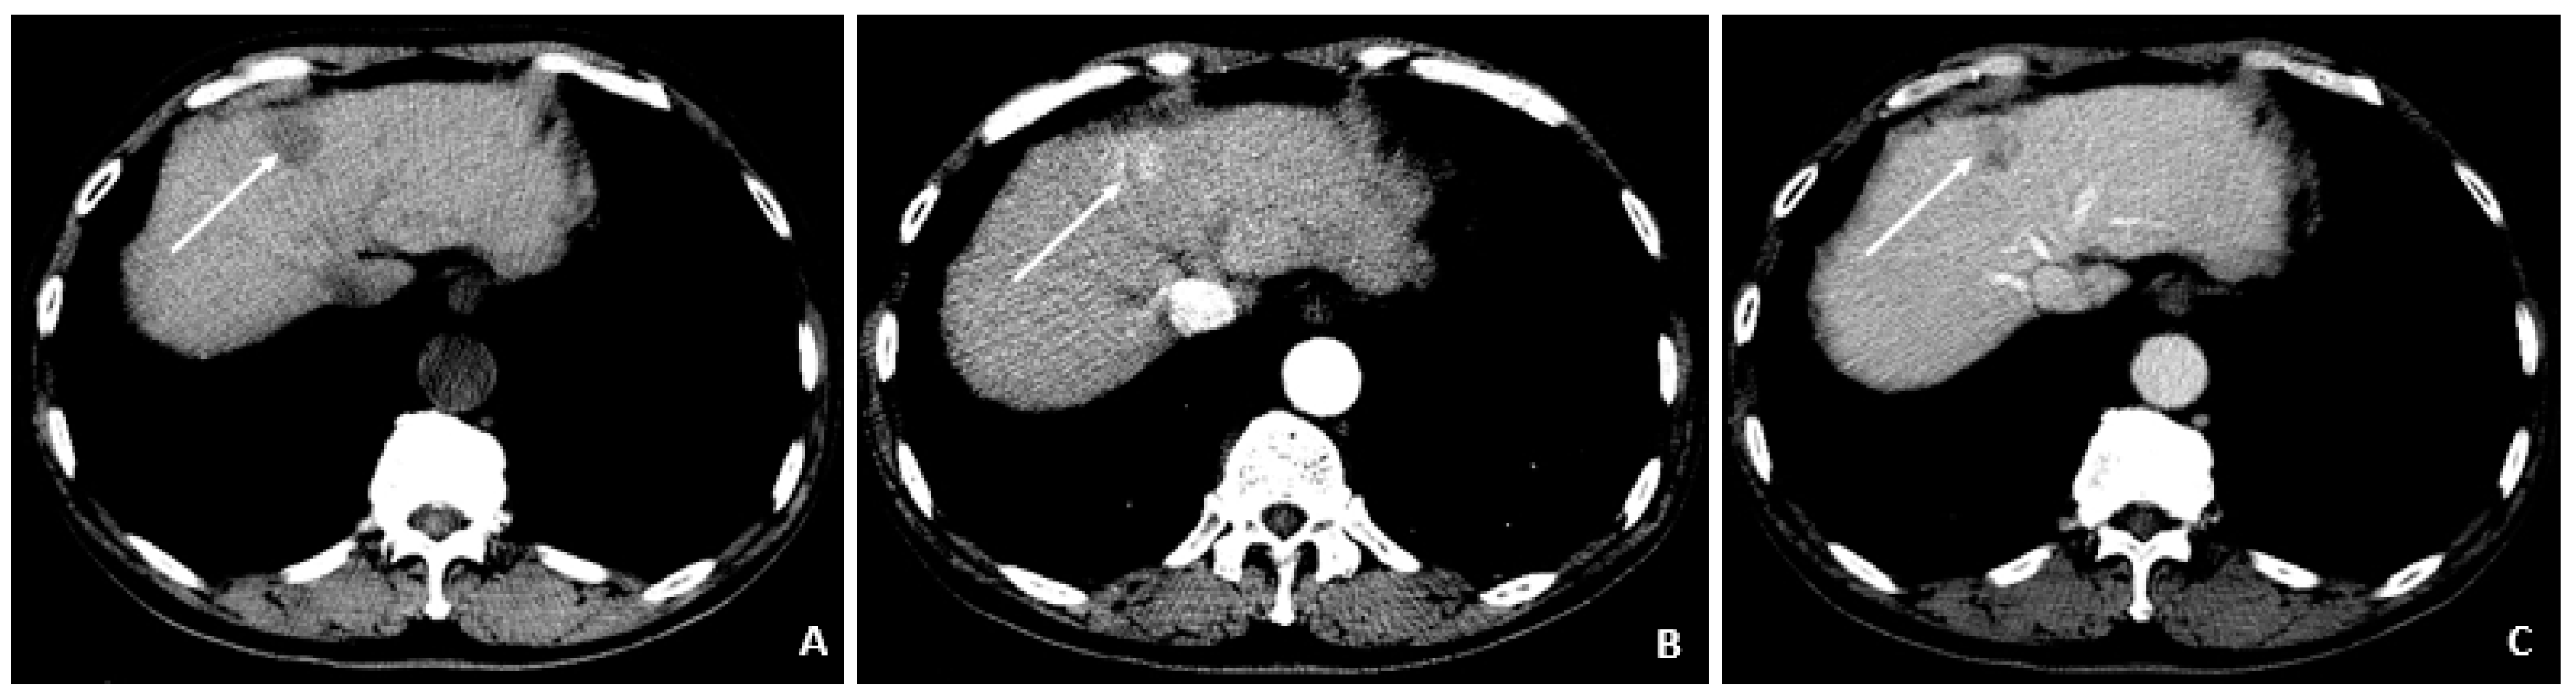

6.4. Case 4: A 50-Year-Old Male

A 50-year-old male was diagnosed with CHB at age 40. With lamivudine treatment for 3 years, he achieved HbsAg seroconversion to anti-HBs and lamivudine was discontinued. Table 4 outlines his course. Five years later, on a follow up examination he was found to have HBV DNA 847 copies/mL, ALT 33 IU/L, and AFP 20.5 ng/mL. An MRI (December 2009) showed a 5 cm lesion consistent with HCC (Figure 1A,B). Repeat AFP was 17.8 ng/mL at time of HCC diagnosis, and AFP-L3% was 75.6. He underwent transarterial chemoembolization (TACE) with successful resolution (Figure 2A,B) and restarted lamivudine. The AFP remained at 3.0 ng/mL, and the MRI showed no evidence of HCC the following year. Two years after initial treatment, the AFP increased to 5.9 ng/mL with 57.5% L3. The MRI next month showed recurrent HCC at the treated site (Figure 3). The patient underwent laparoscopic radiofrequency ablation and therasphere treatment.

Figure 1. MRI at the time of diagnosis of HCC (December 2009). (A) The coronal T2-weighted image shows a mildly heterogeneous mass in the left hepatic lobe (arrow), corresponding to hepatocellular carcinoma. (B) The axial T1-weighted fat-suppressed arterial-phase postcontrast image shows faint foci of hyperenhancement within the lesion, characteristic of HCC.